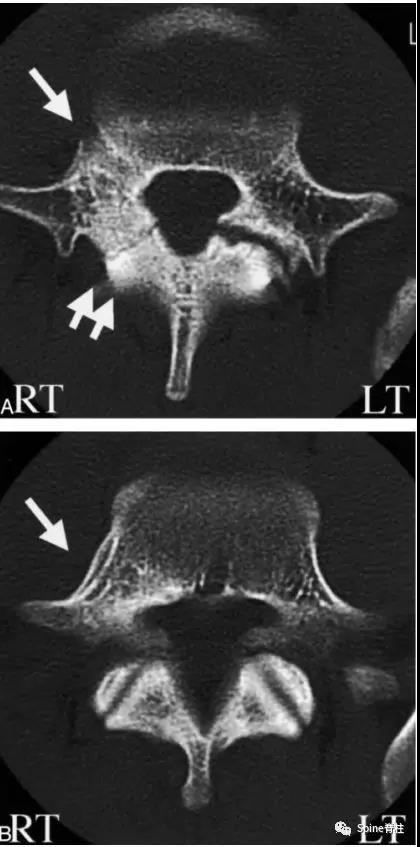

图:6个月复查可见右侧椎弓根裂已愈合(单箭头),但出现右侧峡部裂(双箭头)